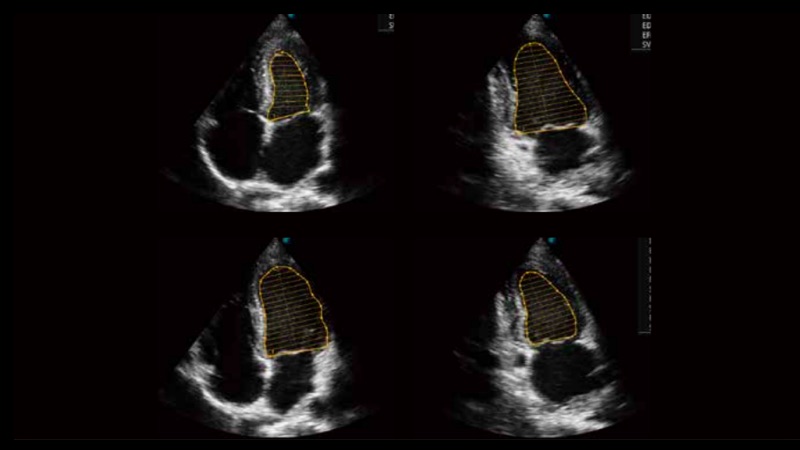

• 心内膜自动描迹Auto EF

自动识别收缩和舒张末期心肌内膜,自动计算射血分数EF值。